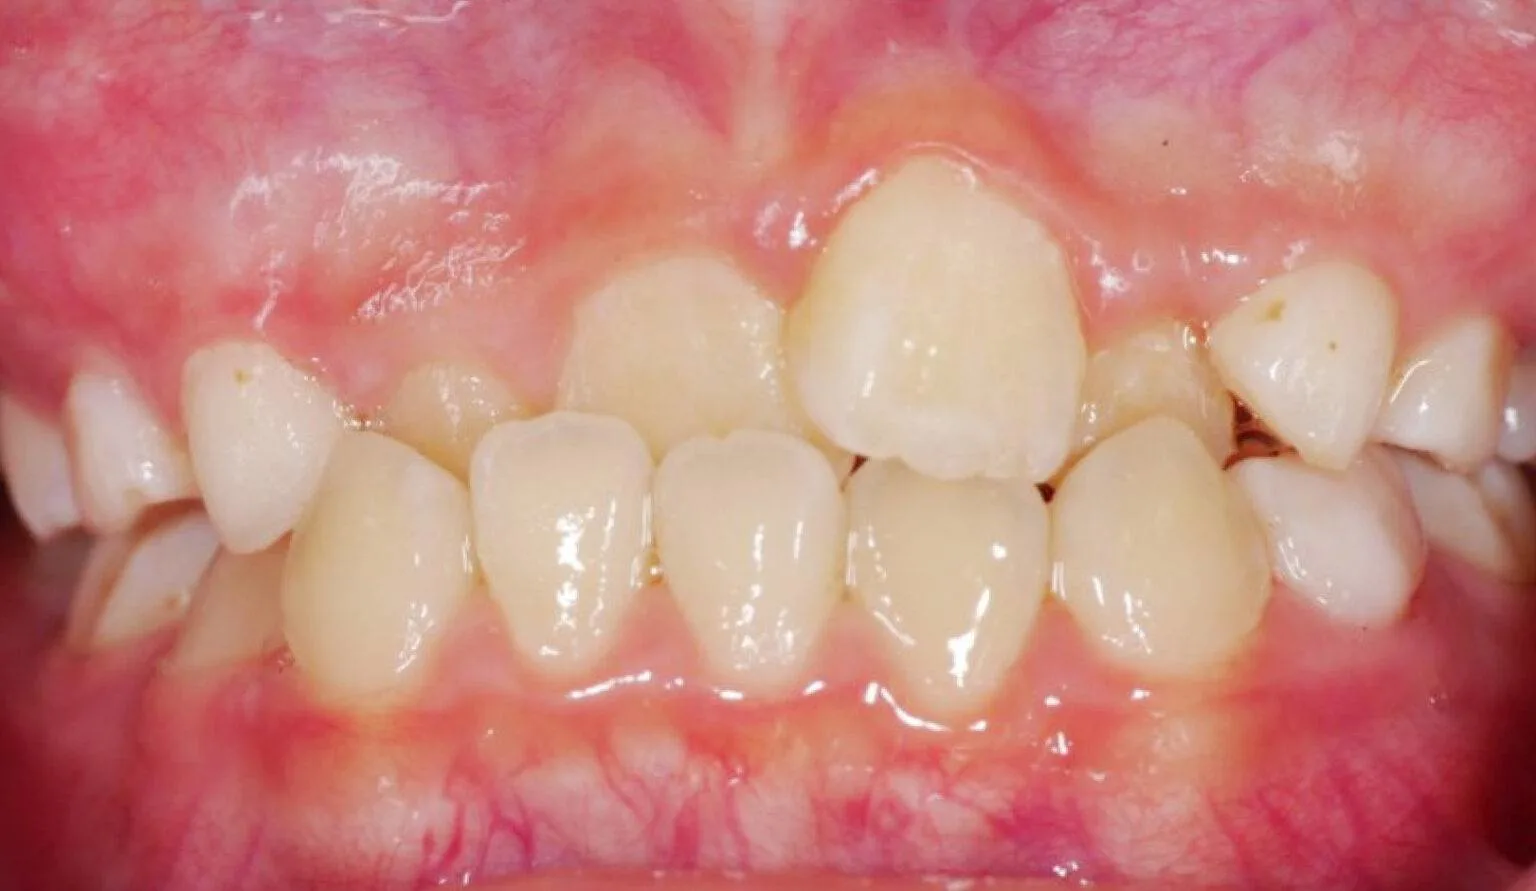

Before overbite treatment showing upper teeth protrusion at SmileBox Dental Clinic After overbite treatment showing corrected bite and balanced smile at SmileBox Clinic